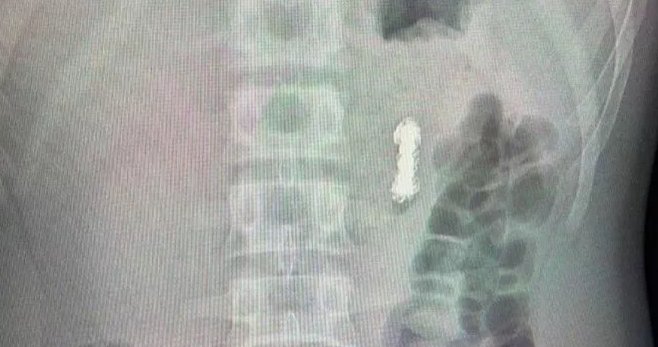

"Мы обнаружили семь магнитов в проекции желудка и еще четыре — в других отделах желудочно-кишечного тракта. За долгие годы они сцепились друг с другом, что привело к перфорации стенки желудка... Мальчику требовалась немедленное оперативное вмешательство: сначала мы извлекли семь магнитов из желудка, но оставшиеся четыре находились глубже по пищеварительному тракту, поэтому достать их эндоскопическим путем не удалось. Поэтому затем хирурги выполнили полостную операцию, в ходе которой извлекли оставшиеся четыре магнита в тонкой кишке", - сказал заведующий отделением эндоскопических методов диагностики и лечения Александр Иноземцев, слова которого приводятся в сообщении.